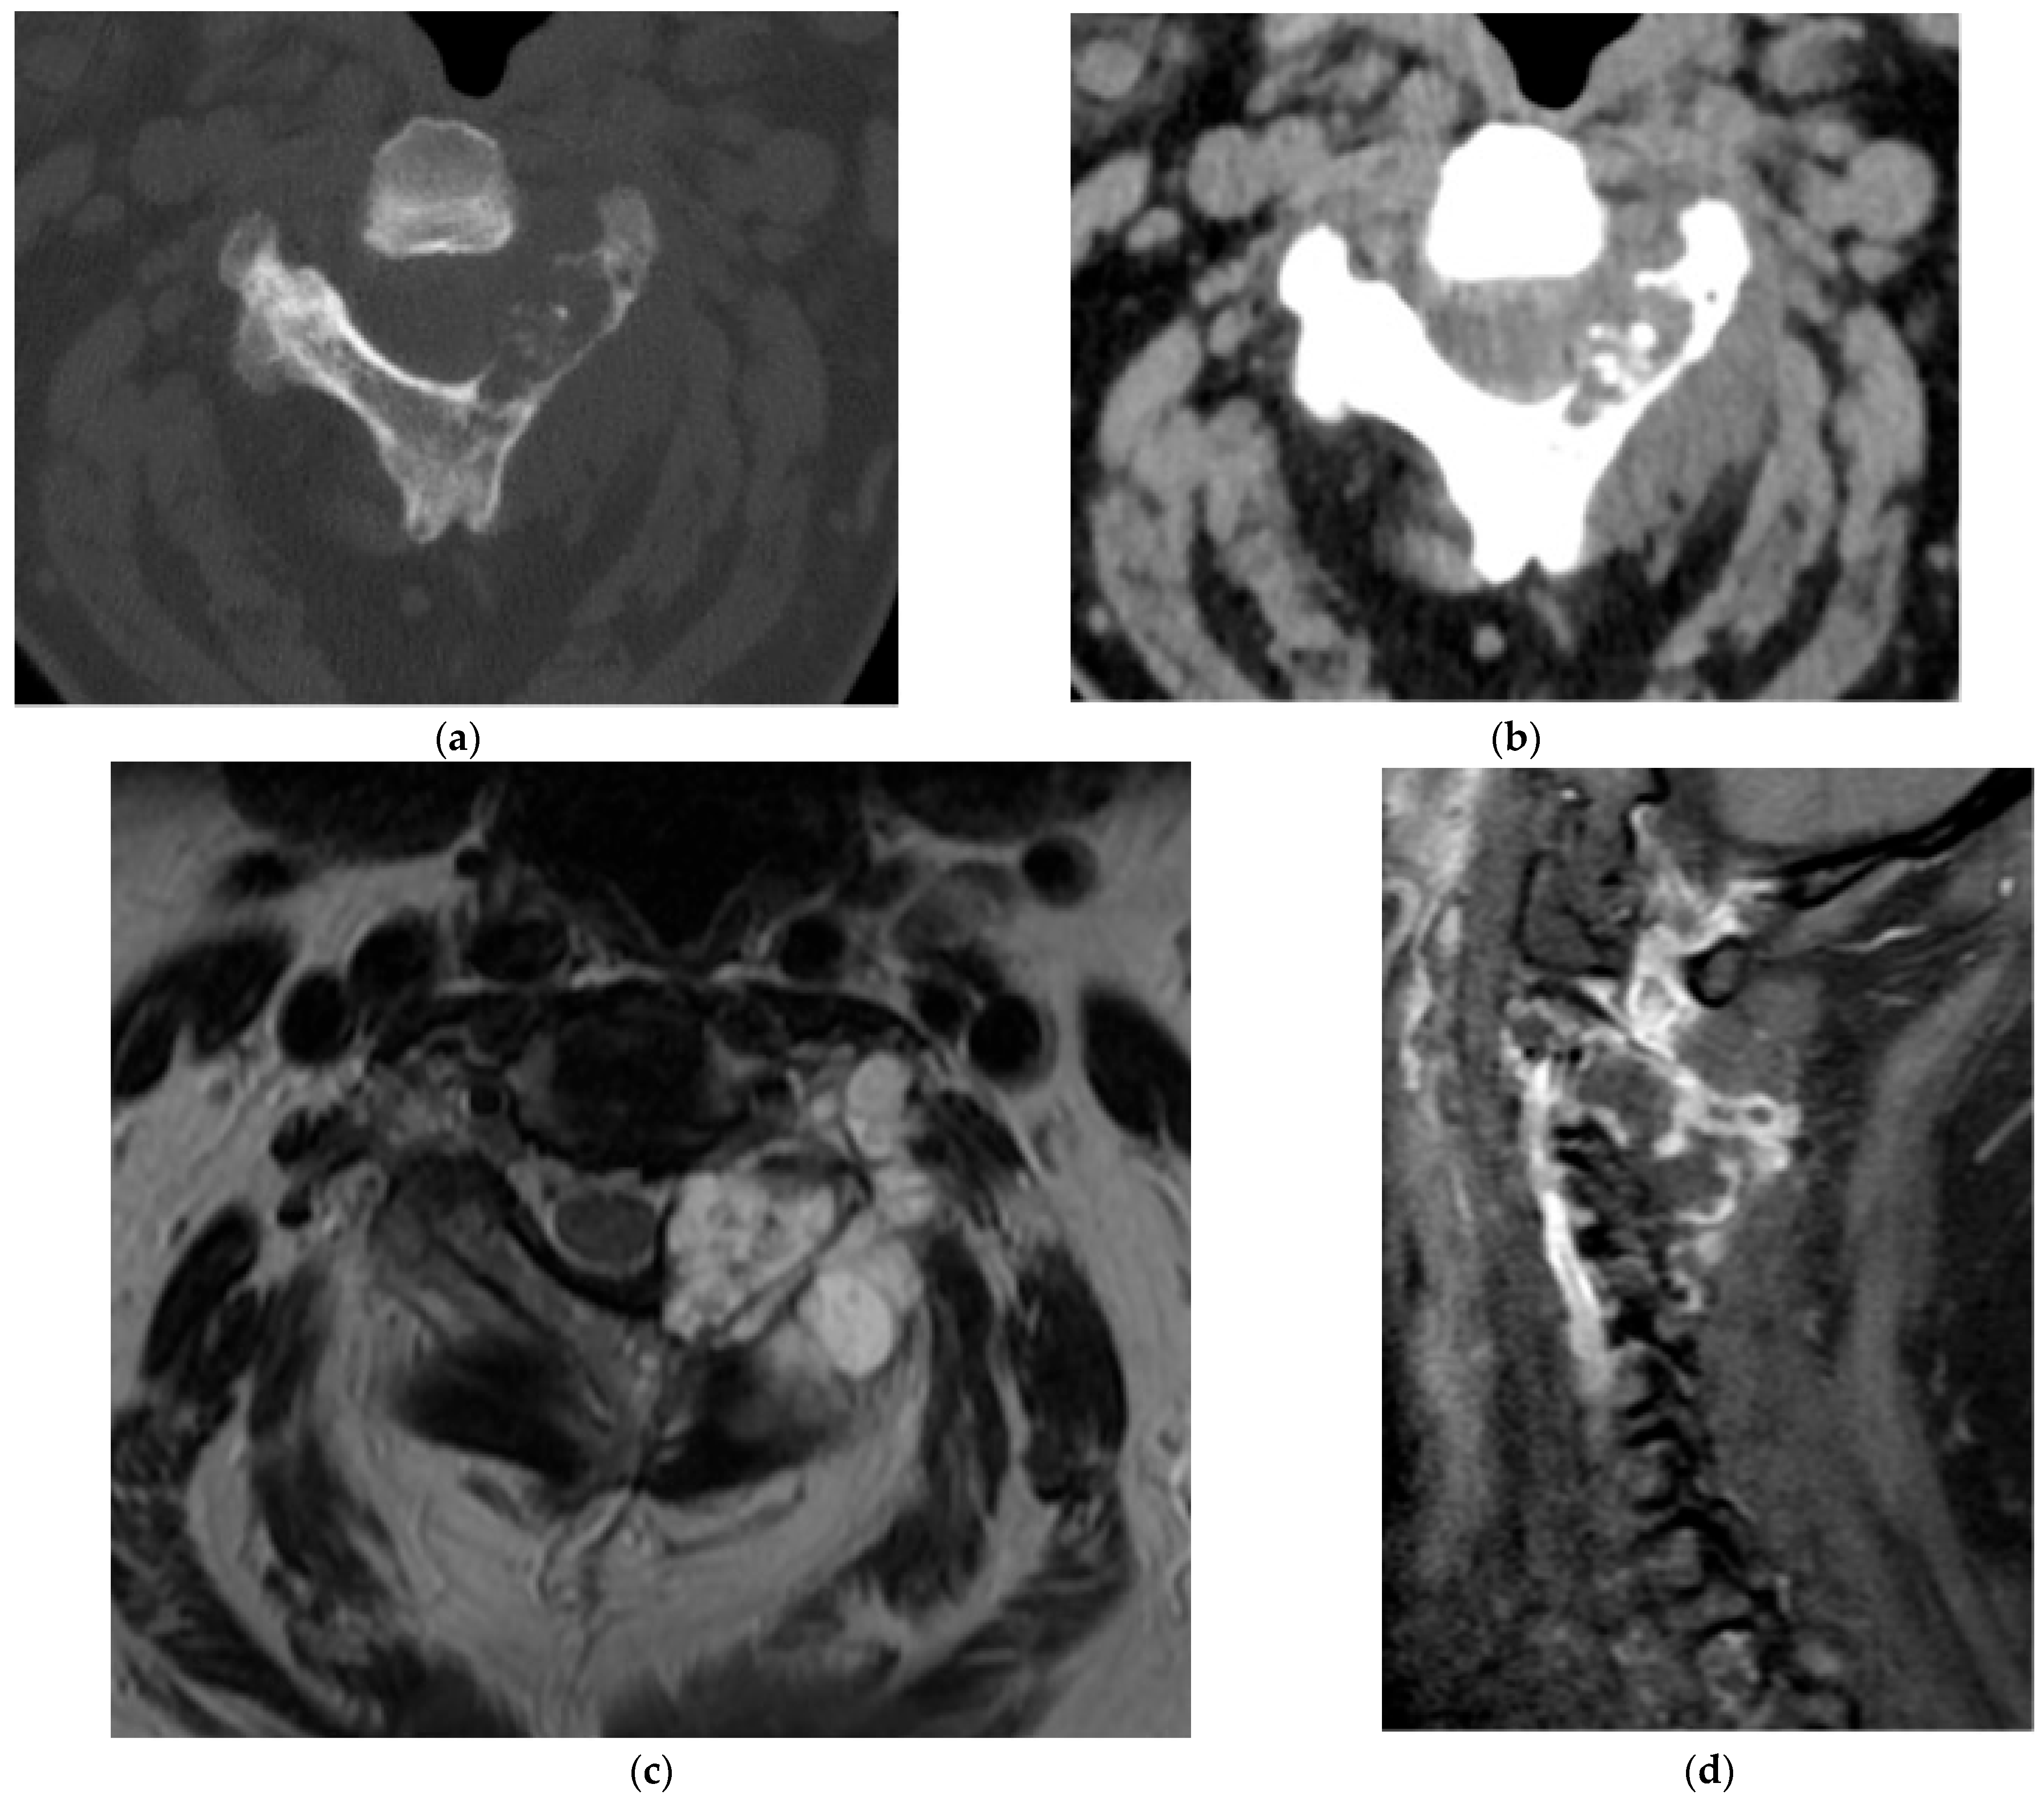

Paget’s Disease

2.10. Primitive Small Round Cell